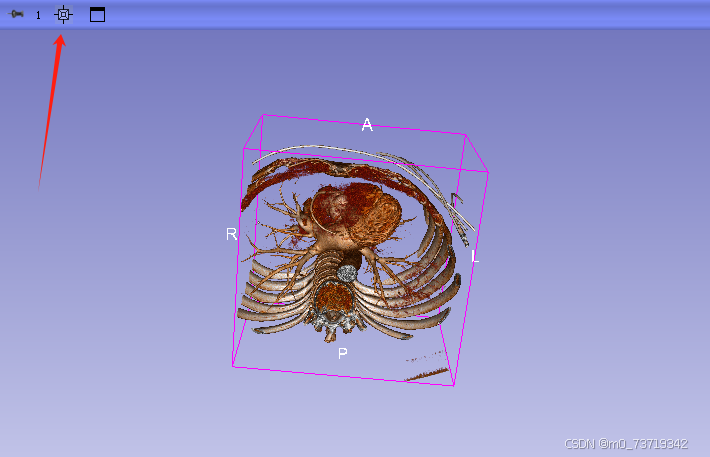

点击第一个视图显示按钮即可查看三维重建图像

补充:三维视图中如何全方位观看重建图像

鼠标左键拉动以中心轴转动三维图像

鼠标滚轮按住可左右平移图像(同样适用于二维视图)